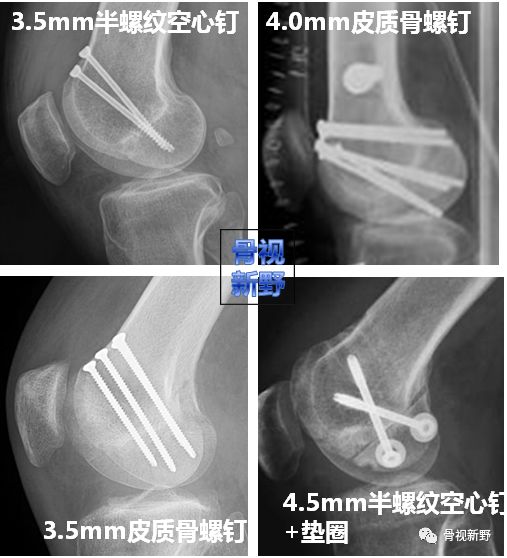

螺钉种类   可用于Hoffa骨折内固定的螺钉种类包括松质骨螺钉、 Herbert钉、 无头加压螺钉等;直径6.5mm的半螺纹空心钉、直径4.5、4.0、3.5mm的皮质骨螺钉/半螺纹空心钉等。

Hoffa骨折到底选择何种螺钉进行固定,文献推荐的固定方式并不统一:

• Benirschke等人(1993)建议使用3.5mm皮质骨螺钉固定;

• Liebergall (2000)等人建议用直径6.5mm的松质骨螺钉;

• Becker等人(2000)用3.5mm、4.5mm的皮钉与6.5mm松钉比较研究发现,这三种钉的固定强度没有显著差异。

• Mize 等人(2001)认为克氏针及可吸收钉的强度不够,建议用4.0mm松质骨螺钉或其它相似螺钉;

• Westmoreland(2002)研究发现小直径螺钉(3.5mm)的抗拔出力量与大直径螺钉相当。

• Jarit GJ(2006)建议关节内骨折用小直径(3.5mm)的皮钉代替大直径的松钉。